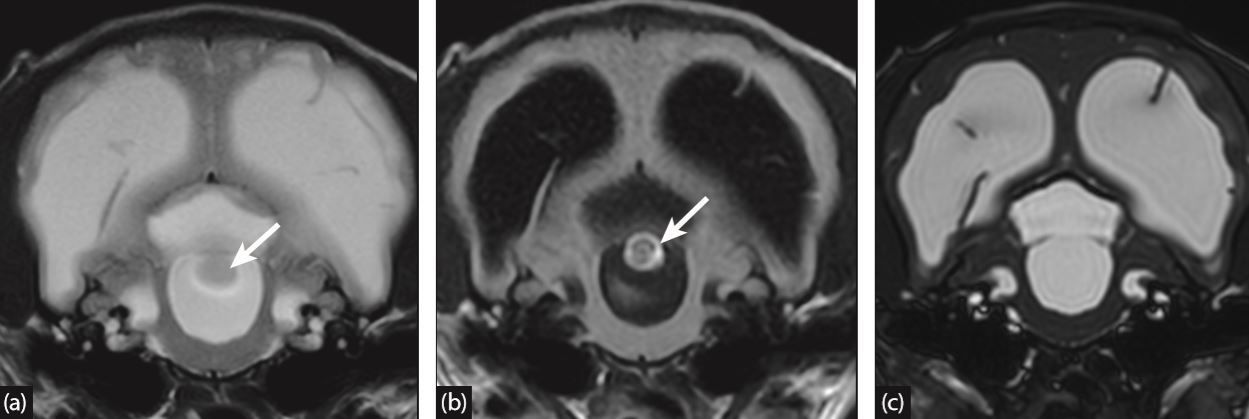

What artifact is this and what sequence?

A

TOF and spin echo due to the lose of signal

11

Q

What artifact is this and what sequence is it?

TOF effect and gradient echo sequence due to gain of signal.

12

What artifact is this?

Slice entery artifact